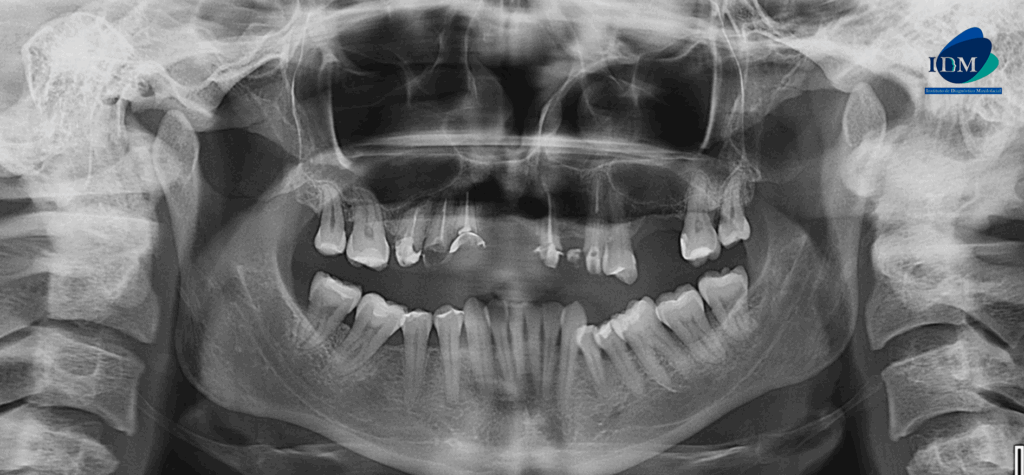

En la radiografía panorámica (Figura 1), se aprecia piezas dentarias con material de obturación, además se evidencia imagen radiopaca definida a nivel apical de pieza 21.

Radiografia Panorámica